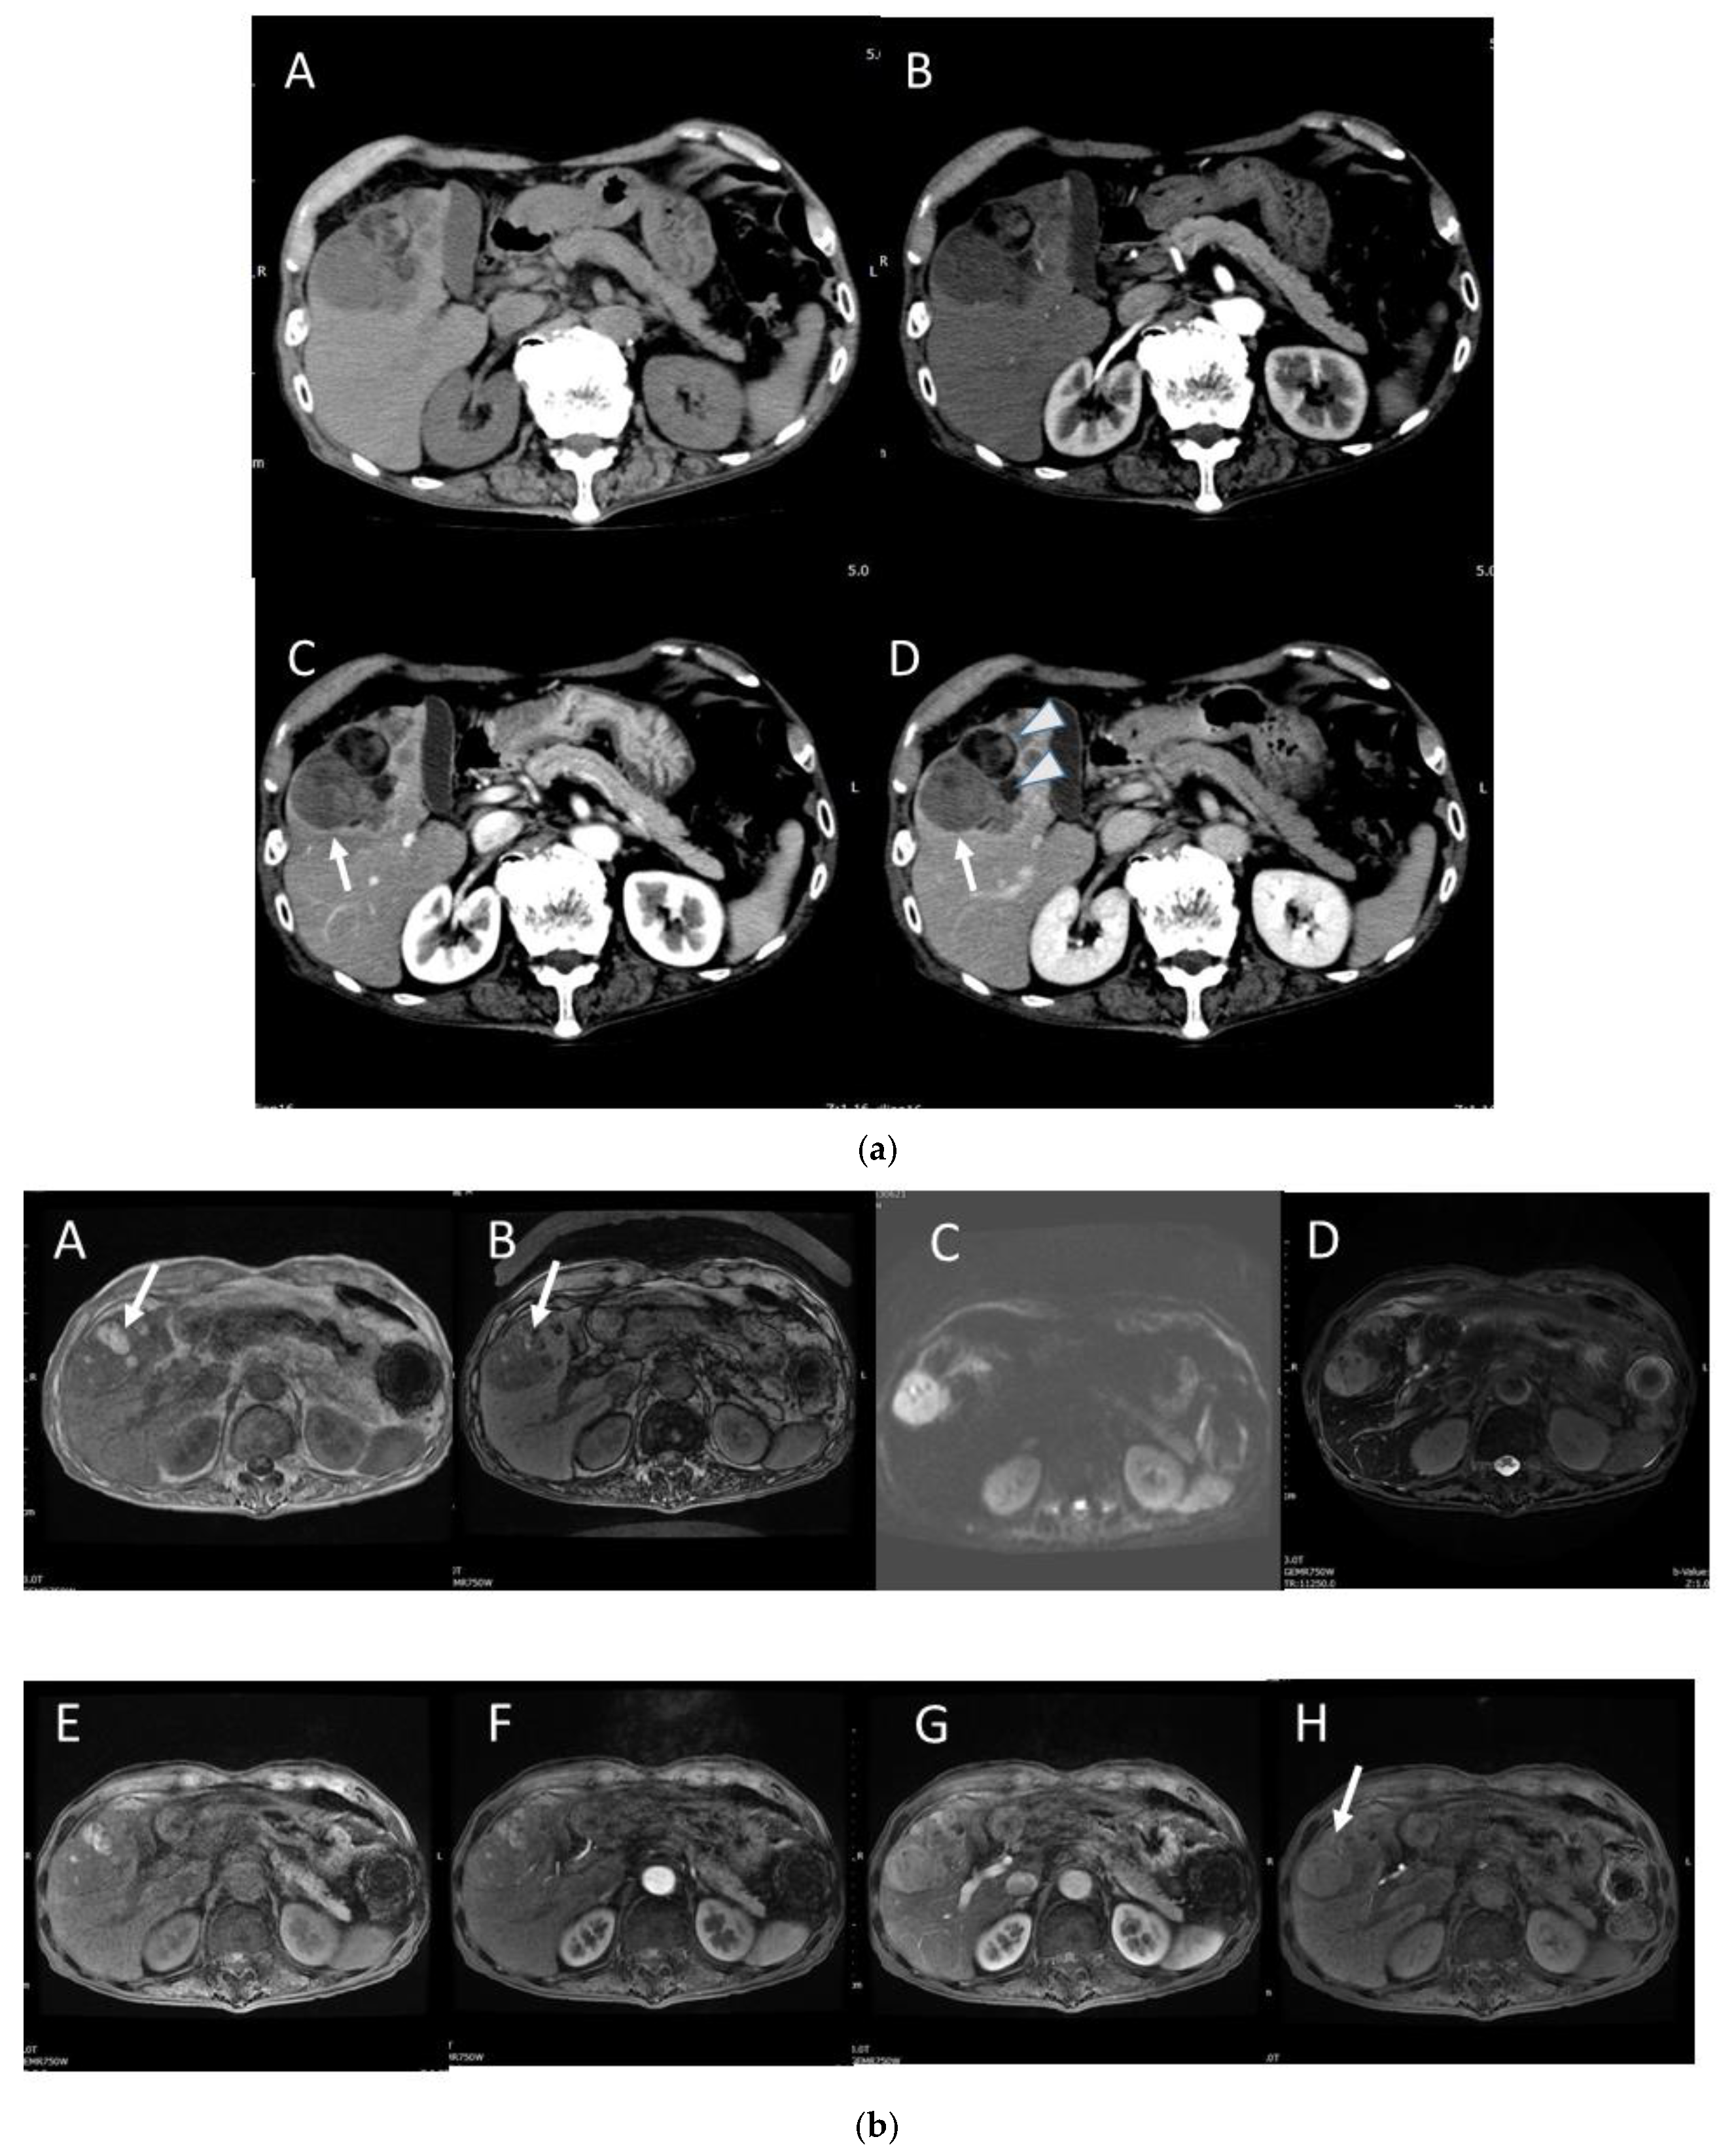

4.2. Early Hepatocellular Carcinoma (Early-HCC)

4.3. Well-Differentiated Hepatocellular Carcinoma (Well-HCC)